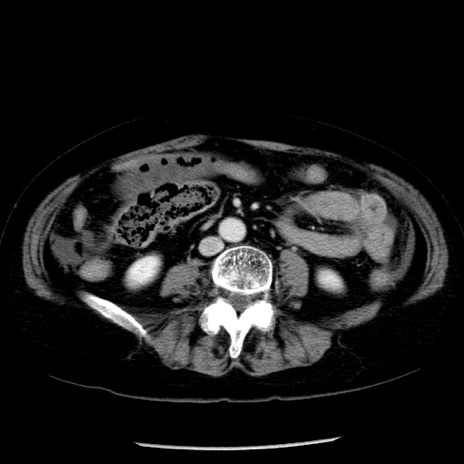

症例13(横断像)

【症例】70歳代女性

【主訴】腹痛、嘔吐

【現病歴】15時間程前(昨晩)より腹痛あり。今朝になっても症状の改善なく、嘔吐あり。腹痛も増悪あり、救急外来受診。

【既往歴】子宮癌全摘術後

【身体所見】意識清明、BP 121/72mmHg、P 74bpm、SpO2 100%(RA)、腹部:平坦・軟、腸雑音ほぼ聴取せず。下腹部・心窩部・臍左上に圧痛あり。反跳痛なし。

【データ】WBC 10600、CRP 0.15